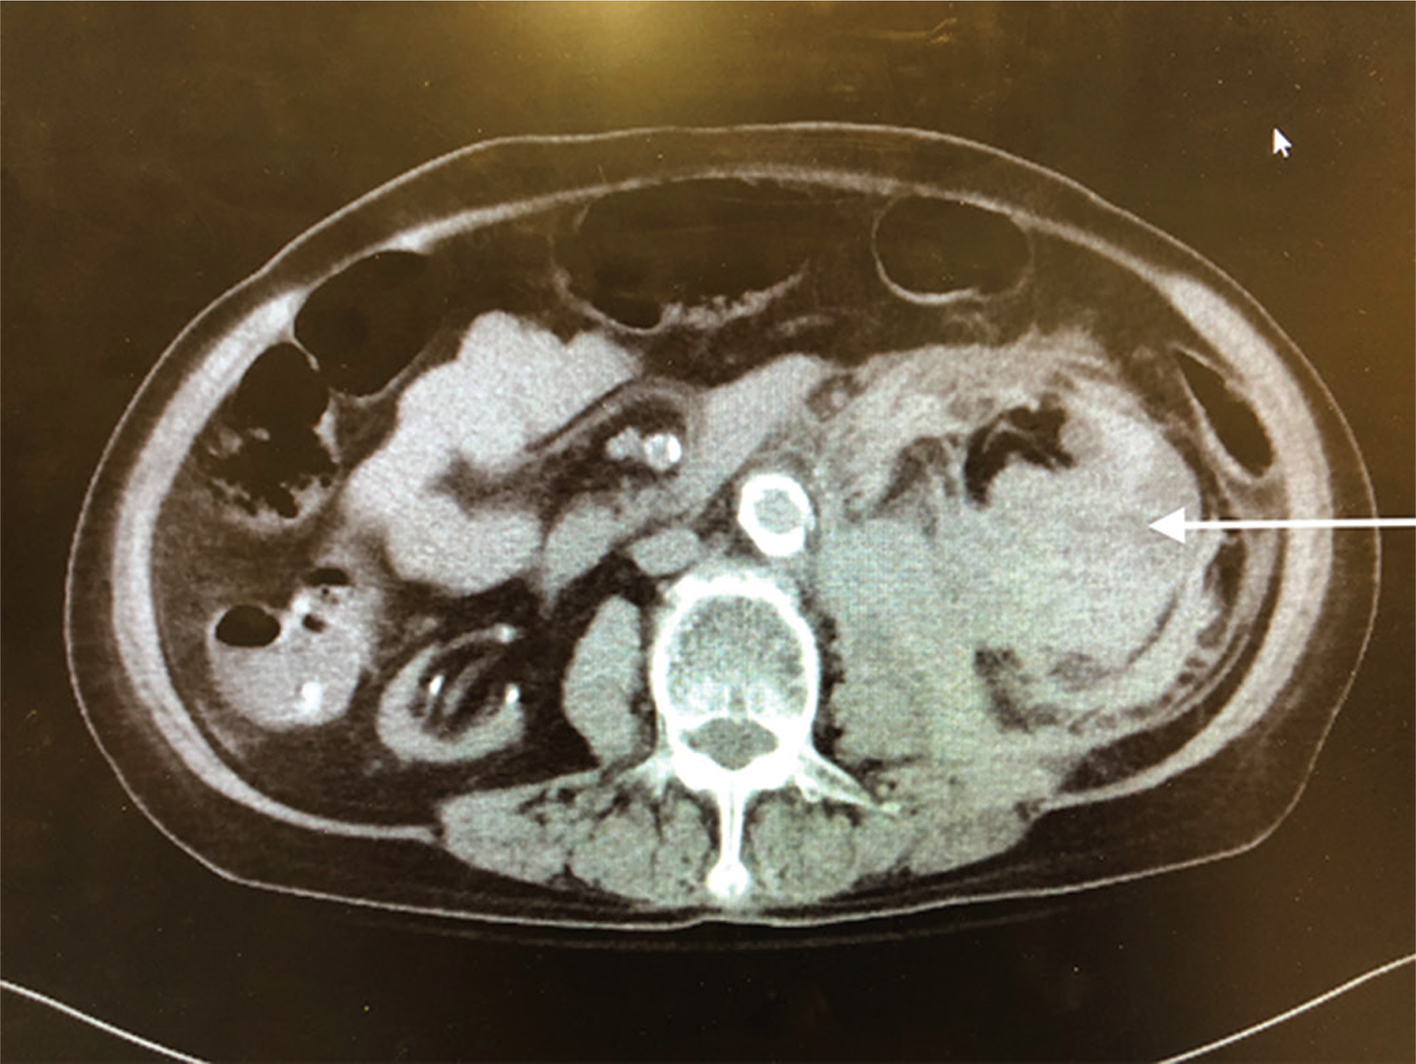

Pathology showed extensive sclerosed glomeruli, marked interstitial inflammation, severe arteriosclerosis, perirenal and renal parenchymal hemorrhage, severe renal artery atherosclerosis, and ACKD. Figurers 1 and 2 show the enlarged left kidney with massive retroperitoneal hemorrhage on CT scan.

Figure 1: Axial CT image of left retroperitoneal hemorrhage.The arrow refers to the large retroperitoneal hematoma.